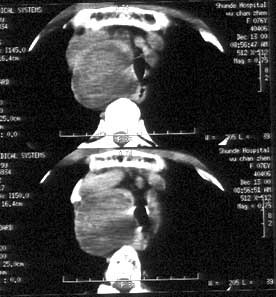

图:甲状腺结节伴点状钙化

实际上,点状钙化即微钙化表现为点状强回声,不论后方是否出现声影,可见于40%~61%的乳头状癌,但也可见于其他良性和恶性病变,如滤泡状癌、分化不良性癌、结节性甲状腺肿、滤泡状腺瘤和桥本氏甲状腺炎等。粗钙化多见于良性结节,尤其是结节性甲状腺肿。边缘钙化指位于甲状腺结节边缘部位的钙化,常见于结节性甲状腺肿,是良性结节的标志。

临床上甲状腺结节点状钙化与甲状腺癌有一定的关系。一般甲状腺结节约有25%出现钙化阴影,而甲状腺癌则有50%~62.5%有钙化。一般认为钙化颗粒越粗大,癌组织分化越好。与医生详细沟通病情,寻找较好治疗方案。